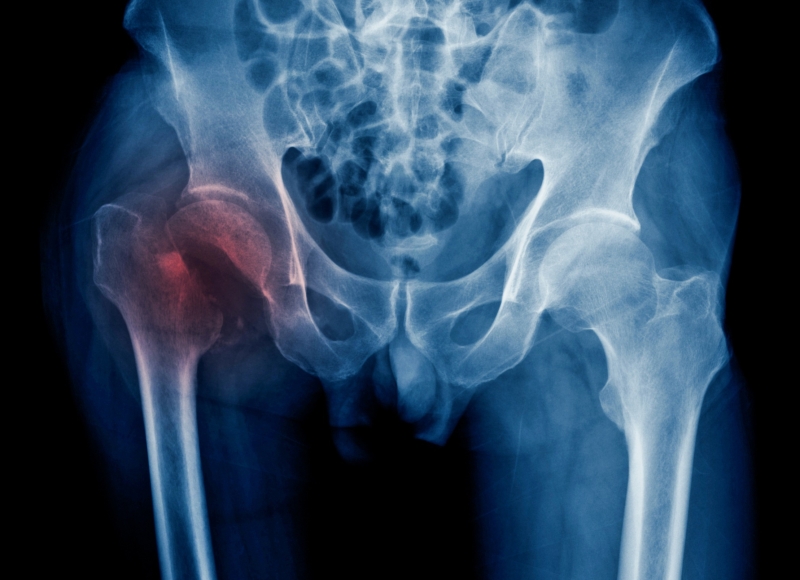

Serious orthopaedic injuries can be life-changing - our experts lawyers can help you make a claim

Orthopaedic medicine concerns the entire body’s musculoskeletal system; bones, tendons, joints, and muscles.

Serious orthopaedic injuries can be life-changing, and injuries to our limbs, spine and neck will affect our everyday lives in many ways; from little things we do each day such as getting dressed to significant things we need to do such as being able to walk. Claims for compensation will need to take in consideration the effect of the injuries now and in the future. The claim will need to explore how much care you need, what appliances you might need, whether your home needs adapting, who will provide care for you, what your financial losses are and what treatment you need now and in the future.